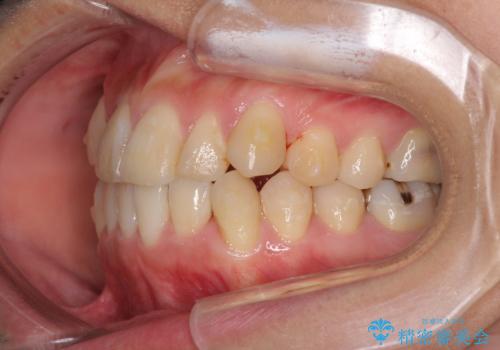

- 上下の八重歯を気にして来院された患者様です。

八重歯の後ろの歯を1歯抜歯し、補助装置(リンガルアーチ)を用いて八重歯の位置を改善し、その後インビザラインにより矯正治療を行うこととしました。

右側のみ上下小臼歯を抜歯したため、上下の正中が右にずれてしまう可能性があります。

また、元々右側は上下が咬み合っていないため、矯正をしても咬み合わないことも考えられました。

治療期間はかかりましたが、正中も合い、綺麗な仕上がりとなりました。